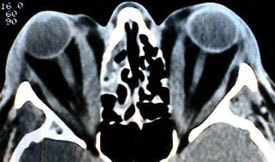

After your clinical examination and review of the relevant orbital CT scans, Dr. Patel will be able to decide the best combination of procedures to give you the best result. We generally operate on one orbit, followed byt the other orbit about four weeks later to allow you to at least be functional with one eye. Our patients find this interval most useful.

A detailed assessment of a CT scan allows us to assess the soft tissue and bony anatomy and changes. All orbital decompressions are not the same. The old-fashioned traditional “we will remove the floor of your orbit” decompressions are not performed in our clinic as they can be complicated by myriad problems including temporary or permanent double vision, malposition of the eyeball (“sunset syndrome”), permanent numbness, and need for further surgery.